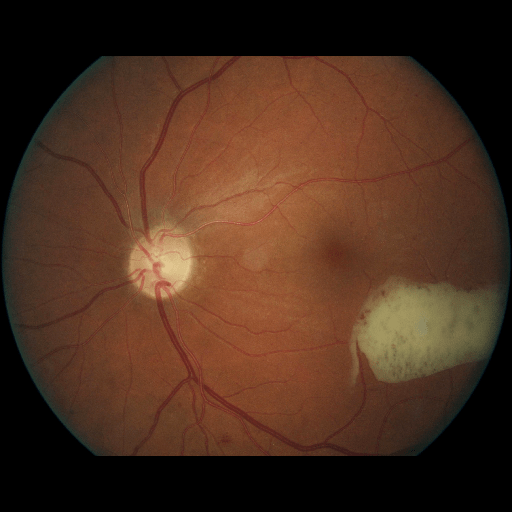

We conducted a case study on diagnosing diabetic retinopathy with ensembles of DL models. For benchmarking the performance of our ensemble-based solutions under the scheme described in Sec.3.3, we used two popular collections of diabetic retinopathy image data, the Kaggle Diabetic Retinopathy dataset [22] (hereafter referred to as “Kaggle-DR”) and the Messidor-2 dataset [23], each respectively consisting of and high resolution images. Diabetic retinopathy is graded into five SLs, as displayed in Figure 2. Following the problem setup used in previous papers [24], we trained models to distinguish the referable (SL2-4) cases from the non-referable ones (SL0 & SL1) (see Section B.1 for more detailed descriptions). We also tested our trained ensemble models on two o.o.d. image datasets (ImageNet [25] and CIFAR-10 [26]) to examine their capabilities of identifying o.o.d. inputs (see Section B in the supplementary materials).

5.1 Distribution of Uncertainty Scores

Distribution of Uncertainty Scores Across Different Severity Levels As explained in Section 3, each uncertainty metric essentially defines an order/ranking among the data points. We conducted an analysis to better understand what data will be assigned high uncertainty under a particular uncertainty metric . Picking out the highest ranked data points (), we calculated the ratio of data points from each SL. Figure 4 summarizes the results as box plots for the Kaggle-DR and the Messidor-2 datasets; additional detailed statistics can be found in Table S.1 in the supplementary materials. From the plot and table, SL1 & SL2 examples account for a higher proportion among the top-ranked uncertain examples across the three ensemble methods. This finding matches our intuition that incipient disease examples (SL1 & SL2) are more likely to be considered uncertain by ensemble methods due to their ambiguity.

The Kaggle-DR dataset comprises high resolution images. The presence of diabetic retinopathy is rated into five different SLs: no-DR (SL0), mild (SL1), moderate (SL2), severe (SL3), and proliferate (SL4), as illustrated in Figure 2. We divided the Kaggle-DR dataset into a development set and a test set, which respectively consisted of and images. The data in the development set were used to train and validate our Deep Learning (DL) models. The Messidor-2 dataset [38] that consisted of images was also used in our experiment as an additional dataset to test the true generalization performance of the models trained on the Kaggle-DR dataset. Images in Messidor-2 dataset were graded into the five SLs as in the Kaggle-DR dataset. Figure S.1 provides an illustration of the datasets used in our experiments.